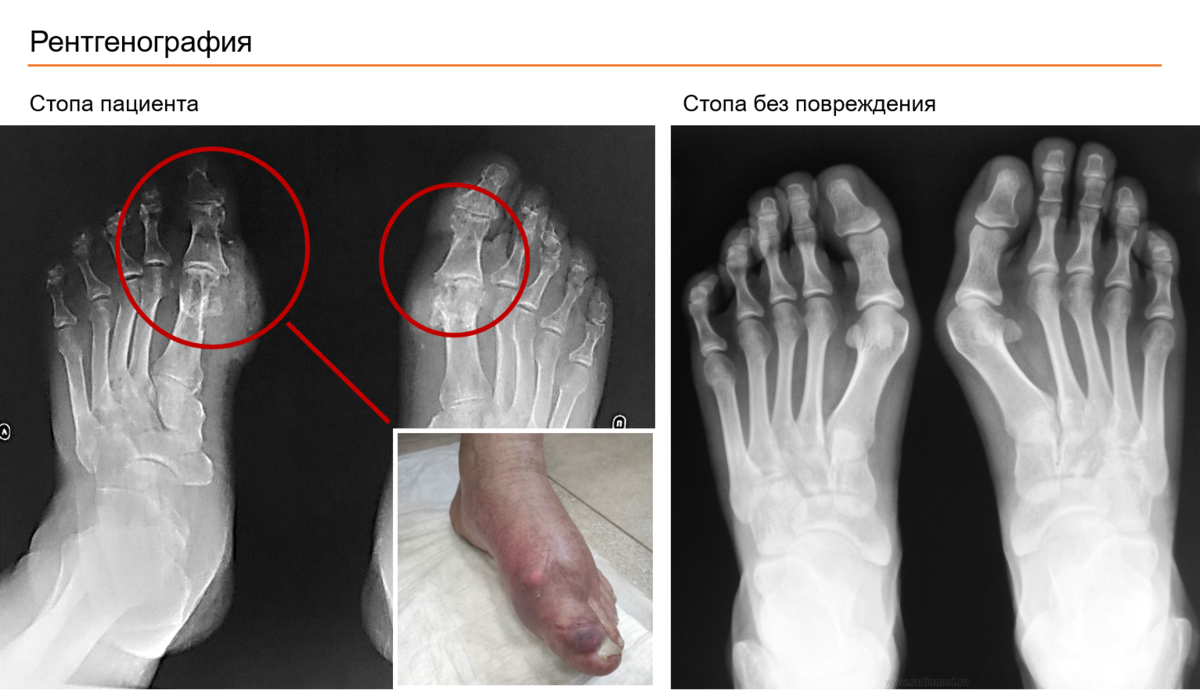

После анализа анамнеза и по данным рентгенографии оказалось, что у пациента никакого «разрушения» костей и суставов нет. А эрозирование косточек больших пальцев было обусловлено внутрикостным отложением солей мочевой кислоты, и представляло собой, так называемый, симптом «пробойника», что довольно часто встречается при хронической тофусной неадекватно леченой подагре. И в данном случае требовалась не ампутация, а адекватное патогенетическое лечение длительно существующей подагры.